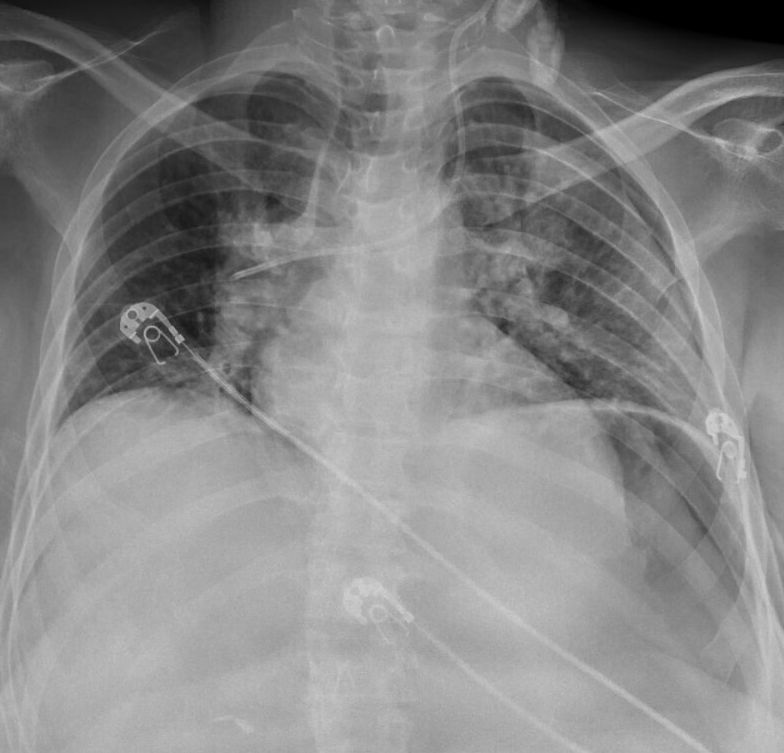

一名46岁的女性,既往有脑瘫、癫痫和严重智力障碍病史,最初因烦躁不安、恶心、呕吐、无法耐受口服摄入以及反复发作的水样腹泻1天而就诊。最初未报告包括胸痛或呼吸困难在内的任何心肺症状。最初临床检查时,患者呈痛苦状态,体温正常(36.7°C),血压低(85/55 mmHg),心率快(110次/分钟),呼吸急促(20次/分钟),在室内空气SPO2为92%。检查发现明显的腹部疼痛伴腹壁强直、颈静脉扩张及双侧肺底啰音。初步实验室检查显示肾功能和肝功能指标升高、乳酸酸中毒以及肌钙蛋白和BNP显著升高。胸部X光显示心脏扩大和肺充血(图1)。ECG示窦性心动过速,心率为110次/分钟,其他无明显异常。

图1. 胸部X光示心脏扩大和肺充血